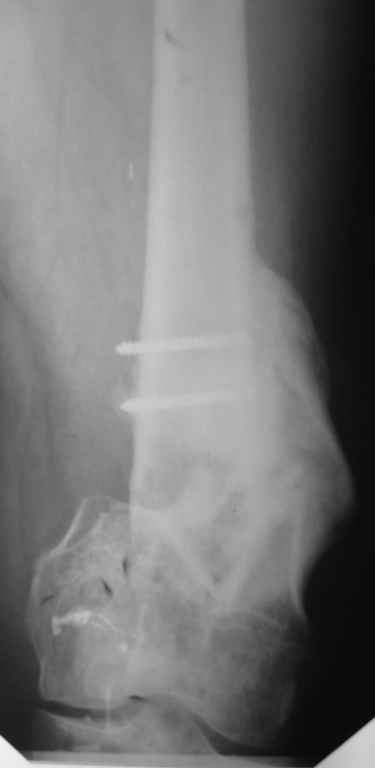

Был оперирован, среди прочего - остеосинтез DHS-фиксатором чреcшеечного перелома правого бедра, DCS-фиксатором остеосинтез оскольчатого чрезмыщелкового перелома левого бедра. Однако, в связи с развитием гнойного коксита были вынуждены убрать DHS-фиксатор и головку. Гнойный свищ правого тазобедренного сустава закрылся сразу после операции. Из-за вторичного смещения и поломки винтов пришлось удалить DCS-фиксатор и сращивать левое бедро внешней иммобилизацией. Прошло чуть более года. Пациент ходит с опорой на обе ноги,пользуется палочкой. Справа относительное укорочение 3см. Слева варус 33гр., тугой ложный сустав н/3бедра. Движения в коленных суставах почти в полном объёме.Перед нами встали вопросы, с чего начать? Протезирование правого ТБС? Восстановление опорности левой конечности? Воспользоваться-ли для этого интрамдулярным остеосинтезом гвоздём с блокированием с ретроградным введением? Стараться при этом восстановить полностью длину, или оставить на потом, на аппаратное решение? Или сразу попытаться использовать аппарат Илизарова? Но боимся потерять колено? Вопросов много.С благодарностью выслушаем все мнения.Заранее спасибоРахматуллин Ринат НургаяновичГКБ N 13 г.Уфа.